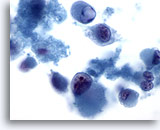

画像 11

肝FNA、肝細胞癌

肝細胞癌の肝細胞。均一に異型が認められ、N/C比が高く、核には不整な核小体が多数みられます。

60倍

画像 11

肝FNA、肝細胞癌

肝細胞癌の肝細胞。均一に異型が認められ、N/C比が高く、核には不整な核小体が多数みられます。

60倍